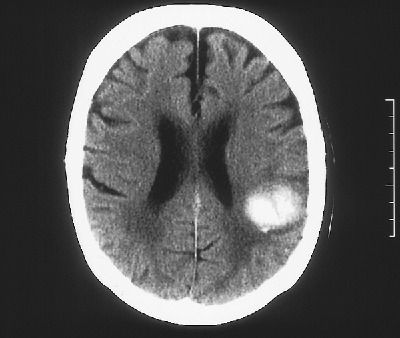

A ct scan can help diagnose hemorrhagic stroke. Hypertensive haemorrhage and lobar haemorrhage are two distinct forms of haemorrhagic stroke. Risk factors specific to hemorrhagic stroke.

In hemorrhagic stroke, bleeding occurs directly into the brain parenchyma.

Stroke series video 1 of 7: This bleeding can occur either within the brain or between the brain and the skull. • brain imaging is a crucial part of the emergent evaluation. A hemorrhagic stroke that occurs inside your brain is also called an intracerebral hemorrhage.